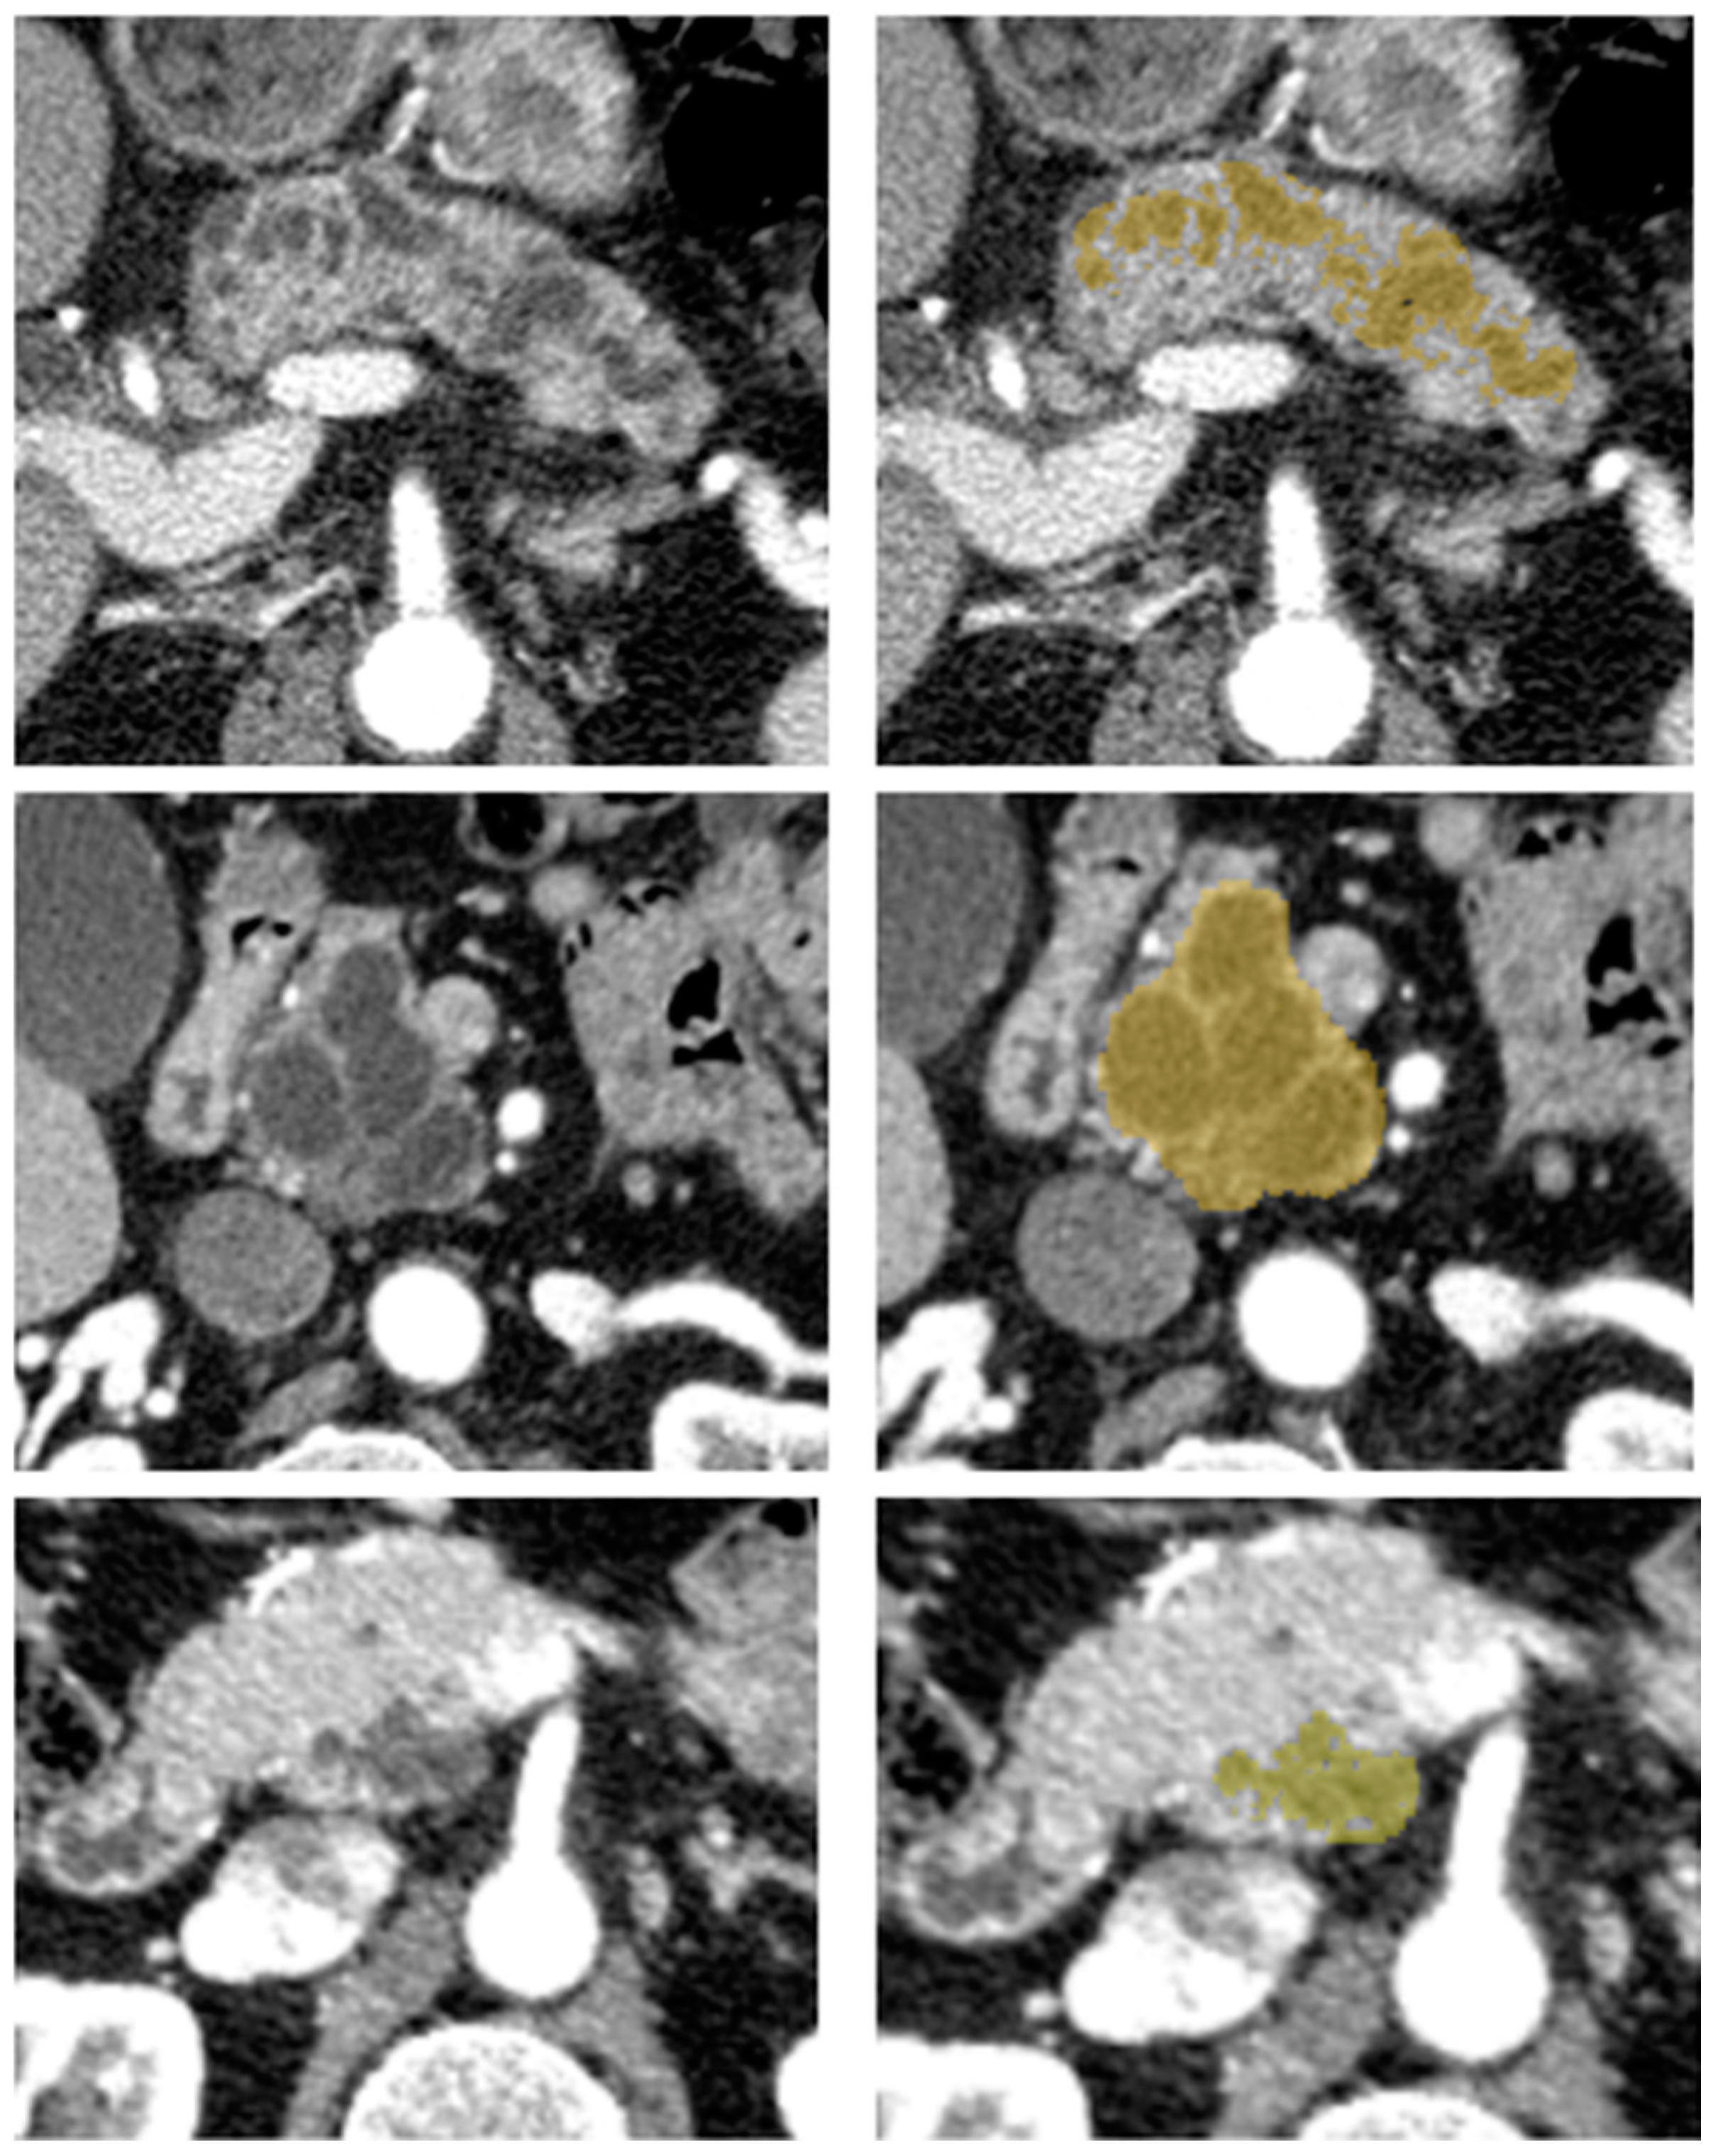

Image segmentation was performed by one reader with five years of abdominal imaging experience. Before segmenting the cohort’s tumors, consensus segmentation was performed on 15 exams, including challenging cases with a senior radiologist who had more than 20 years of experience in IPMN diagnosis. The reader was blinded to the pathologic analysis but not blinded to the type of surgery. Using a web-based medical segmentation tool (MedSeg [34]), delineation of the volume of interest (VOI) was drawn in a semi-automatic manner, covering the tumor’s volume as represented in Figure 2. The semi-automatic segmentation consisted of a smart brush with a variable radius and adjustable minimum and maximum intensity thresholds, preventing voxels with an intensity outside these user-defined thresholds of being segmented, reducing, this way, the number of necessary corrections when compared with a non-thresholded brush segmentation. If multiple cysts were present with no clear evidence of worrisome features, the most conspicuous or larger cyst was selected in the pancreas portion according to the type of surgery (duodenopancreatectomy, left pancreatectomy, enucleation, others). The reader was given no specific directions regarding the display settings such as thresholding and window level. The reader visually inspected the semi-automated segmentation and made free hand corrections when appropriate to reproduce the tumor’s closest shape and avoid including adjacent fat and vessels.

Figure 2.

Examples of different IPMN on axial contrast-enhanced CT scans in the pancreatic phase (left) and with a semi-automatic outlined tumor in yellow (right).